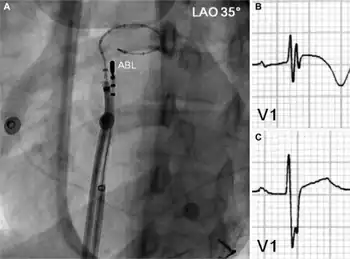

Catheter ablation involves advancing several flexible catheters into the patient's blood vessels, usually either in the femoral vein, internal jugular vein, or subclavian vein. The catheters are then advanced towards the heart. Electrical impulses are then used to induce the arrhythmia and local heating or freezing is used to ablate (destroy) the abnormal tissue that is causing it. Originally, a DC impulse was used to create lesions in the intra-cardiac conduction system.[6] However, due to a high incidence of complications, widespread use was never achieved. Newer procedures allow for the terminating of diseased or dying tissue to reduce the chance of arrhythmia.

One type of catheter ablation is pulmonary vein isolation, where the ablation is done in the left atrium in the area where the 4 pulmonary veins connect.[7][8]